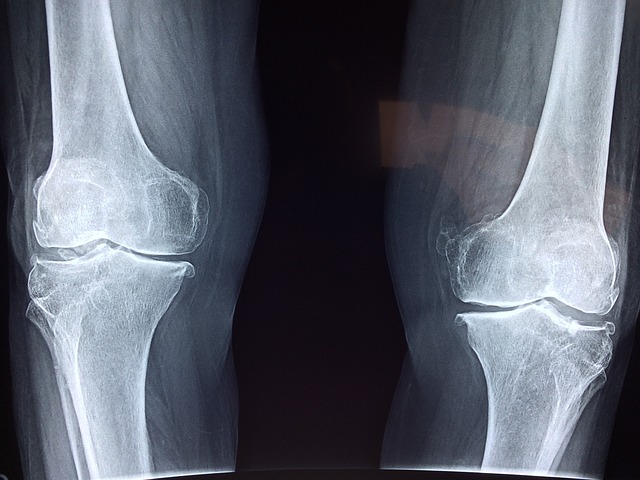

연골은 관절을 보호하는 부드러운 조직으로, 관절의 원활한 움직임을 돕고 충격을 흡수합니다. 연령 증가, 부상, 또는 특정 건강 상태로 인해 연골이 손상되거나 마모될 수 있으며, 콘드로이친은 이러한 연골의 손상을 늦추거나 관절 건강을 개선하는 데 도움을 줄 수 있습니다.

- 관절 건강 증진: 콘드로이친은 연골의 수분 보유 능력과 탄력을 유지하는 데 중요한 역할을 하여, 관절의 윤활을 개선하고 부드러운 움직임을 촉진합니다. 이는 특히 관절염이 있는 사람들에게 통증을 감소시키고 일상 활동의 품질을 향상시킬 수 있습니다.

- 연골 손상 완화: 콘드로이친은 연골 세포의 새로운 성장을 촉진하고 연골 분해를 억제함으로써 연골 손상을 줄이는 데 도움을 줍니다. 이는 연골 마모를 늦추고 장기적으로 관절의 건강을 유지하는 데 기여할 수 있습니다.